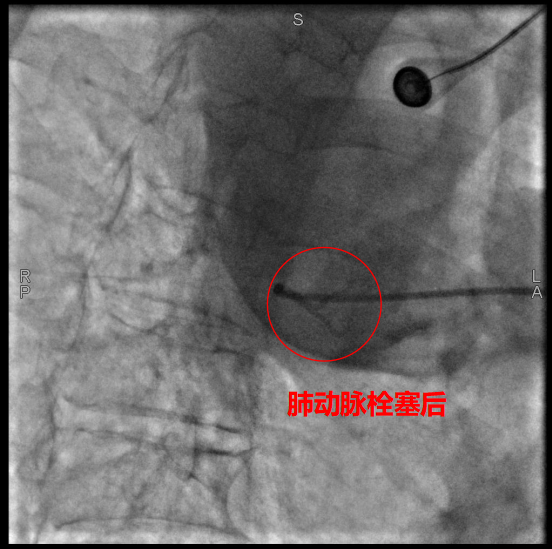

術中,數字減影血管造影(DSA)顯示患者右側支氣管動脈及胸廓內動脈增粗紊亂,末梢血管可見造影劑點狀外溢,明確為主要出血責任血管。團隊采用400?μm栓塞微球及560–710?μm明膠海綿顆粒,對出血動脈遠端實施精準栓塞,實現“末梢血管封堵”;同時,對肺動脈分支血栓相關區域也予以栓塞處理,以全面控制咯血來源。術后造影確認出血完全停止,患者安返病房后未再咯血,胸悶、氣促等癥狀顯著緩解。